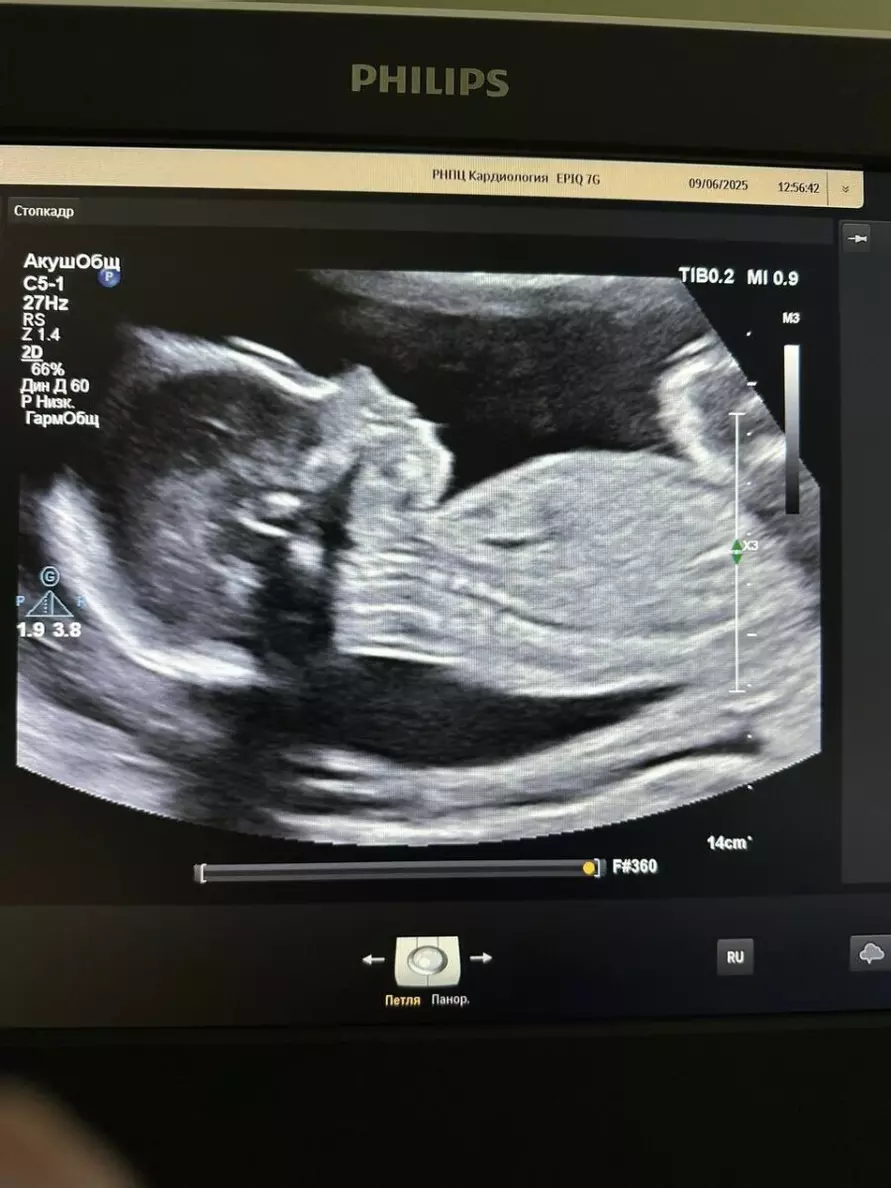

Как пояснили в Минздраве, такую операцию в Беларуси проводили впервые. О её результатах решили рассказать уже после того, как малыш появился на свет. В июне 2025 года, когда малышу пришлось пережить своё первое хирургическое вмешательство, ему было всего 23 недели, причём не от роду, а от зачатия.

Для того, чтобы удалить образовавшуюся в его левом предсердии миксому, была проведена высокотехнологичная кардиохирургическая операция в условиях искусственного кровообращения. Несмотря на то, что сама по себе опухоль является доброкачественной, не удалять её было нельзя - она повышает риск тромбоэмболий (инсульт, инфаркт) и нарушения кровотока, что могло привести к печальным последствиям для самого малыша и его 33-летней мамы.